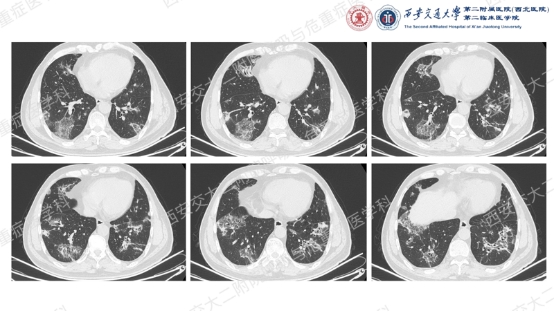

让我们一起从影像入手,看看这名患者的胸部CT特征:双肺多发斑片、实变和磨玻璃影,胸膜下和支气管血管束周围分布为主,病灶无明显空洞、钙化,可见散在支气管充气征,反晕征(中心磨玻璃影 + 外周环形实变影)尤为显著,伴典型“环礁征”(病灶边缘呈结节状隆起,类似环礁形态)。基于这些特征性影像学表现,同时排除细菌、真菌、结核感染及结缔组织病、肿瘤等常见病因,临床诊断隐源性机化性肺炎(COP)。

COP是一种病因不明的机化性肺炎(OP),属于特发性间质性肺炎的亚型,由肺部不明原因损伤引发的局部炎症及修复异常所致。其临床以急性或亚急性起病为特征,影像学表现具有“五多一少”的典型特点,是诊断及鉴别诊断的核心依据:

①多态性:可呈斑片状、实变状、团块状、条索状、地图状、结节状、粟粒状、网织状等各种形态,以前4种比例较高,每例患者多同时具有2种以上的形态。

②多发性:COP多为两肺多发性病灶。

③多变性:病灶有明显的游走性,具有此起彼伏的特点,多数病例在1周内可见观察到病灶的明显变化。抗感染治疗基本不影响病灶的变化。

④多复发性:文献报道的复发率多在13~58%之间。

⑤多双肺受累:两侧中下肺分布为主,占88%;沿着胸膜分布占96%,不累及胸膜占40%。

⑥蜂窝肺少见:仅有少数晚期重症COP出现蜂窝肺,发生率为4%。